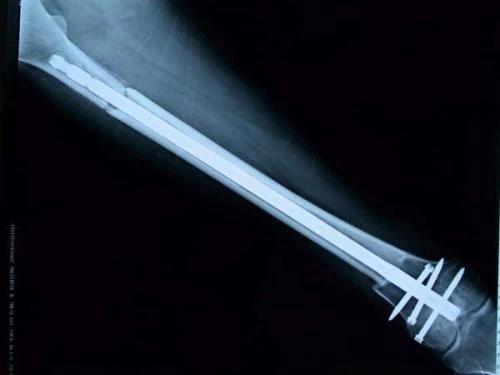

保肢治療指經(jīng)典型骨肉瘤在多學科團隊醫(yī)生共同努力下完成的新輔助化療、保肢手術和輔助化療等一系列治療總稱,其目的是在提高患者生存率的前提下,減少局部復發(fā)、盡量保留良好的肢體功能。肢體經(jīng)典型骨肉瘤保肢治療方法如下圖所示:

新輔助化療的目的是盡早殺滅遠處微小轉(zhuǎn)移灶,縮小腫瘤及周圍炎性水腫反應區(qū),以利于后續(xù)的保肢手術;觀察腫瘤對化療的敏感性,為進一步指定個體化的術后化療方案奠定基礎。骨肉瘤新輔助化療下的保肢治療如下圖所示: